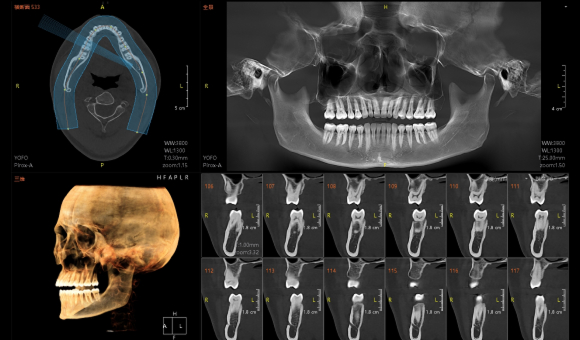

实现3D“一成三”成像

单圈扫描可同时获得CT、3D全景及3D正侧位影像,患者无需多次摆位。

实现非拼接大视野成像

Pirox-A采用多射源并行扫描技术,360°扫描一圈,即可实现非拼接超大视野成像。